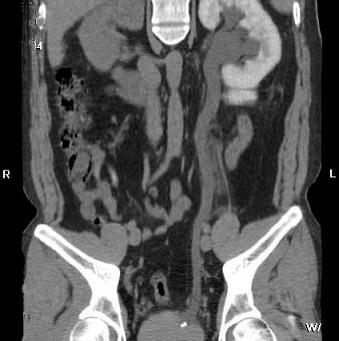

问题 男,29岁,下腹部疼痛不适伴血尿2 月,CT检查如图,下列说法错误的是 ( )

选项 A、考虑为盆腔静脉石 B、考虑为左输尿管下端结石 C、左侧输尿管扩张 D、左肾积水 E、左侧输尿管末端膀胱入口处可见一高密度影

答案 A